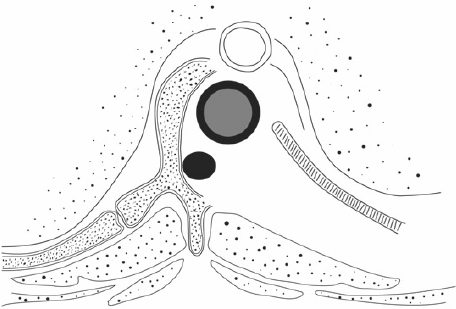

Cancer of the Spine

Cancer of the spine, both secondary and primary, are of particular interest to this practice. Dr Mobbs has undertaken further training in complex spine cancer surgery and reconstruction.

Click on the thumbnails for enlarged view